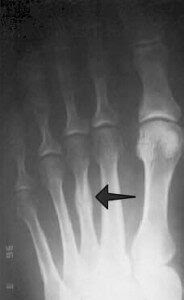

‘Tja,’ zegt mijn huisarts als hij een tijdje aan mijn voet heeft gedraaid, geduwd en geklopt en precies weet waar de pijn zit. ‘Eigenlijk weet ik het niet. Het lijkt op een marsfractuur…’ Hij legt uit dat dat een scheurtje is in het middenvoetsbeentje en dat het zo genoemd wordt omdat het voorkomt bij militairen die heel lange marsen hebben gelopen. Heb ik onlangs een hele lange wandeling gemaakt? Nou nee. ‘Maar het kan best dat ik iets op m’n voet heb laten vallen wat ik niet meer weet. Zoiets gebeurt me wel eens.’

Woensdagochtend fiets ik naar het ziekenhuis (fietsen gaat prima), waar door een energieke dame binnen een paar minuten een foto wordt gemaakt van mijn voet. Tien minuten later komt ze me vertellen dat er een heel klein scheurtje in een middenvoetsbeentje zit.